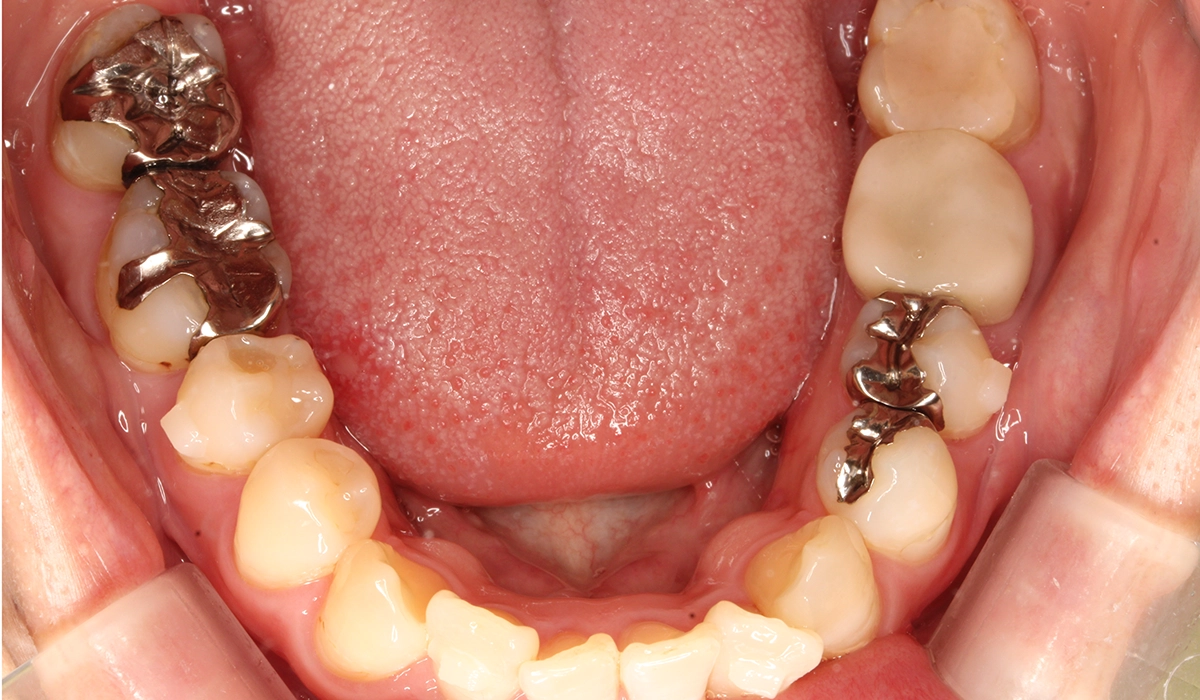

術前:上顎

術前:下顎